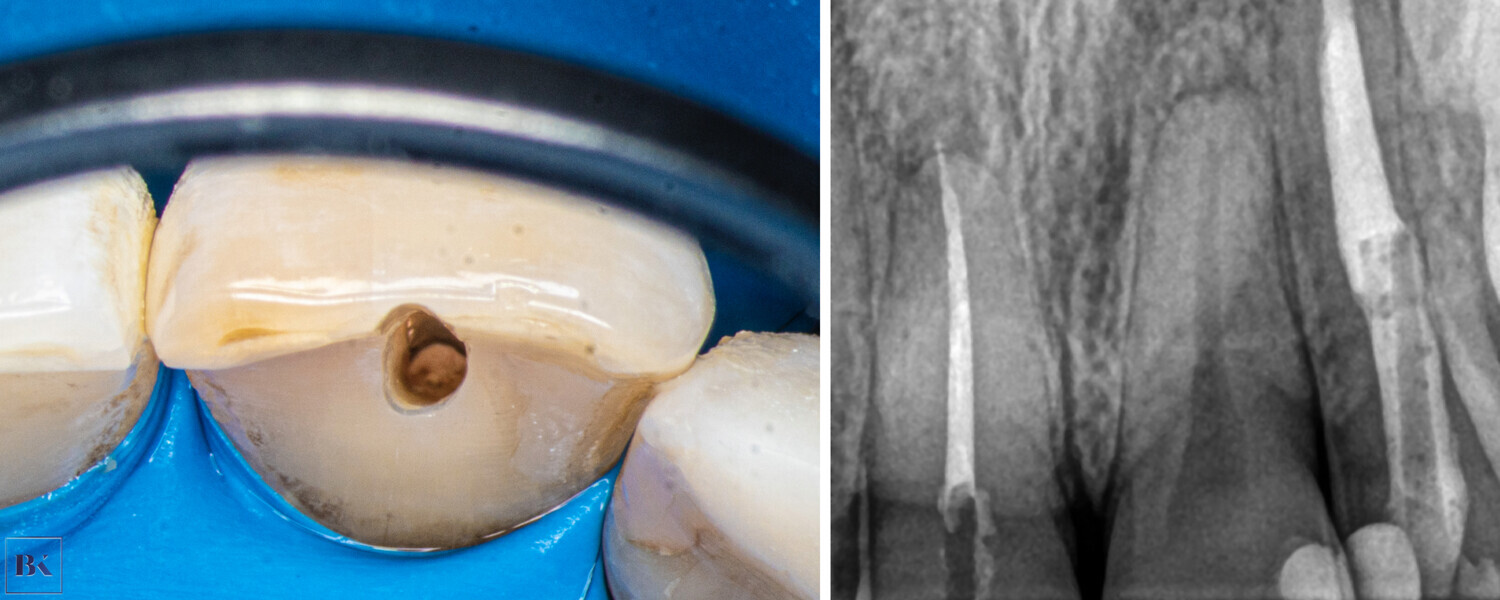

A 30-year-old female patient presented to the dental clinic complaining of constant pain of the left central incisor. Moreover, the patient was unhappy with the aesthetics of both incisors and had a history of trauma (Fig. 14). CBCT examination was performed with the 9000 C 3D (Fig. 15). The CBCT scan revealed a periapical lesion around the left central incisor and PCO for 12 mm from the incisal edge. The root of the left incisor was approximately 5 mm shorter than the root of the right incisor, which could indicate apical inflammatory root resorption. Moreover, PCO was present in the right central incisor up to 12 mm from the incisal edge, and an irregular shadow in the central area of the root was present. This image could indicate internal resorption. There was no lesion in the periapical area. In both teeth, the size of the canals in the periapical area were narrower than the typical size of the canals in the central incisors.

Fig. 14: Intra-oral view of the initial situation. Visible discoloration of the right central incisor.

Figs. 15a–c: CBCT scan, sagittal (a & b) and coronal planes (c). Pulp canal obliteration was visible in both teeth, and a periapical lesion was present around the left incisor. Internal resorption in the right incisor was suspected.